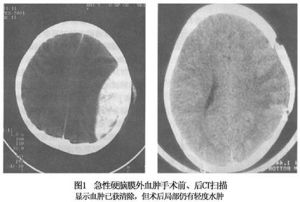

2.CT掃描

表現為呈雙凸鏡形密度增高影,邊界銳利,骨窗位可顯示血腫部位顱骨骨折,同側腦室系統受壓,中線結構向對側移位。

急性硬膜外血腫的治療,原則上一經診斷即應施行手術,排除血腫以緩解顱內高壓,術後根據病情給予適當的非手術治療。一般若無其他嚴重併發症且腦的原發損傷較輕者,預後均良好。死亡率介於10%~25%之間。實際上這類患者死亡的主要原因並非血腫本身,而是因腦疝形成後所引起的腦幹繼發性損害所致,因此,必須做到早期診斷、及時處理,才能有效地降低病死率。目前,CT掃描使早期診斷成為可能,CT可清晰顯示血腫的大小、部位、腦損傷的程度等,使穿刺治療部分急性硬膜外血腫成為可能,且可連續掃描動態觀察血腫的變化,部分小血腫可保守治療。